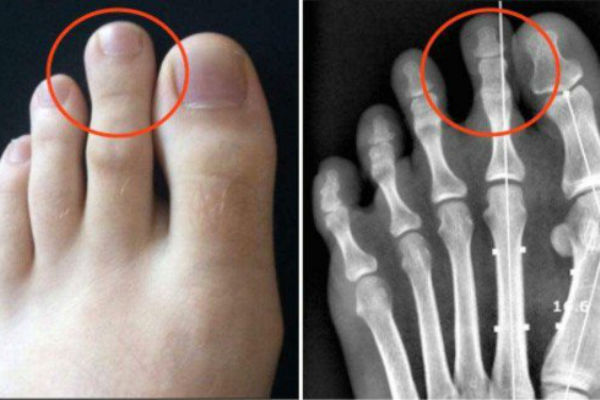

Ovo vam je sigurno privuklo pažnju, makar sa gledišta estetike! Radi se o tzv. Grčkom stopalu, pri kojem je drugi nožni prst duži od prvog i javlja se kod svega 14% stanovništva

Grčko stopalo može donijeti probleme i uzrokovati bol, ukoliko se ne koristi adekvatna obuća.

Imajte na umu da, kada hodate ili trčite, vaše noge trpe većinu tjelesne težine, tako da je oblik stopala nešto što znatno utiče na cjelokupan osjećaj. Osobe sa grčkim stopalom češće trpe bolove u stopalima, a to je nešto što se ne smije ignorisati!